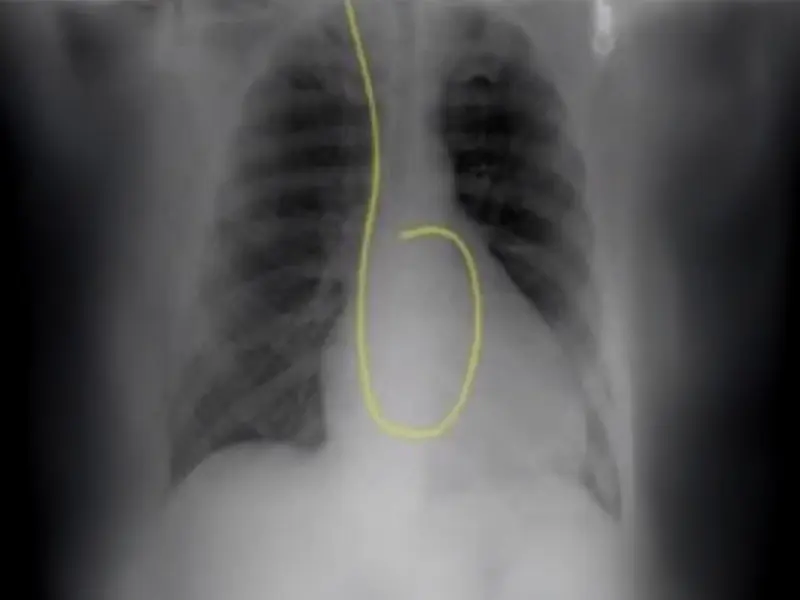

Placement of a pulmonary artery catheter (PAC), commonly known as a Swan-Ganz catheter, provides hemodynamic data that is vital for clinicians treating patients with acute decompensated heart failure or cardiogenic shock. While routine use has been shown to not be beneficial, there are many instances in which hemodynamic monitoring through the use of a Swan is highly indicated.

“Hemodynamic monitoring by PAC or the Swan-Ganz is a diagnostic tool that by itself cannot improve a patient’s condition,” says Cesar Y. Guerrero-Miranda, MD, FACC, Medical Director, Mechanical Circulatory Support, Advanced Heart Failure and Transplant Cardiology, Baylor University Medical Center, part of Baylor Scott & White Health. “The focus must not be whether PAC use is associated with better outcomes, but how to translate the hemodynamic information obtained from PAC into appropriate interventions and therapies that lead to better outcomes.”